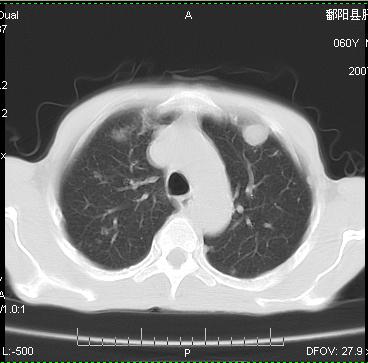

标题: CT12370:男.60岁.咳嗽发热胸痛. [打印本页]

标题: CT12370:男.60岁.咳嗽发热胸痛.

两肺示有散在大小不等类园形边缘不整密增高影.

考虑多发性转移瘤.请各位老师指导.

双侧胸壁见多发结节软组织密度灶,两肺内见广泛结节状、面团样影,两肺及胸膜多发性转移瘤。支持

根据:病变确实是多发,但大部分边缘不光滑,欠规整,密度不均匀。也就是说“大部分病灶不是典型转移瘤的表现”。转移瘤可以不典型,但如此大部分不典型,却是很少见的。结合发烧病史,考虑肺多发小脓肿或其他炎性病变,如霉菌等感染!建议痰培养,抗炎治疗后复查!